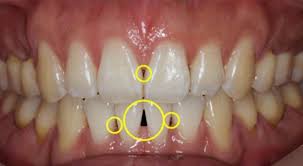

- 치은염(잇몸염증): 치석, 치태로 인한 세균 감염

| 치은염 | 잇몸 붉어짐, 출혈 동반 | 스케일링, 위생관리 |